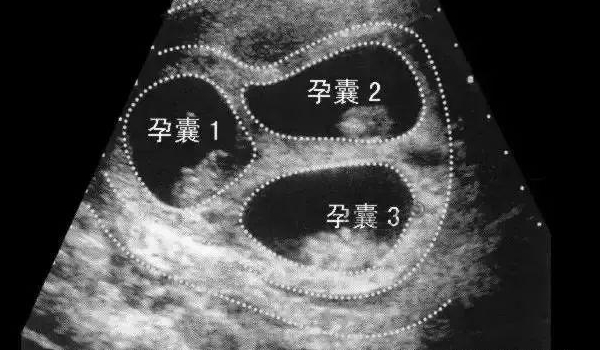

已生男孩孕囊图片

孕囊作为妊娠最早期的超声可见结构,其形成始于受精卵着床后5-7天。正常发育的孕囊直径每日增长约1mm,妊娠5周时平均直径达5mm。胚胎学研究表明,孕囊壁由滋养层细胞和胚外中胚层组成,其形态受HCG水平调控。2025年《人类生殖》期刊发表的研究证实,孕囊形状变异系数与染色体异常存在统计学关联,但尚未发现与胎儿性别的确定性联系。

现代妇产科学采用经阴道超声测量孕囊三个径线(长径、横径、前后径),计算形态指数(SI)。标准测量要求在妊娠6-8周进行,探头频率不低于7MHz。最新发布的《妇产科超声操作规范(2025版)》强调,孕囊评估需结合卵黄囊直径(正常2-6mm)和胎芽长度。三维超声重建技术可提升测量精度达92%,但临床研究显示不同性别胎儿的孕囊容积差异无统计学意义(p>0.05)。

针对民间"孕囊形状辨性别"的说法,2025年北京大学医学部牵头开展了多中心研究。纳入的8600例妊娠数据显示,椭圆形孕囊组与圆形孕囊组的胎儿性别分布无显著差异(χ²=1.32,p=0.251)。日本学者在《超声医学杂志》发表的研究同样指出,所谓"长条形孕囊生男孩"的准确率仅为51.2%,与随机猜测无异。现有证据表明,孕囊形态主要反映着床位置和子宫张力状况。